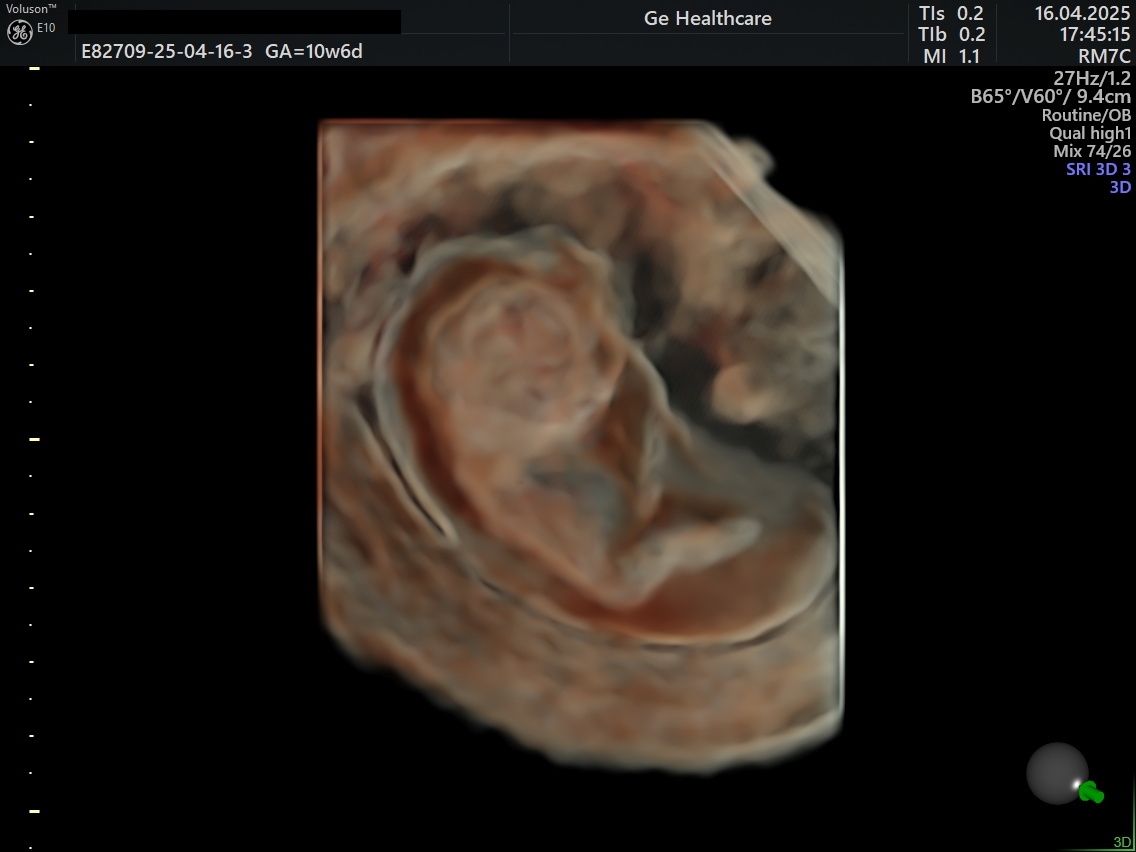

Mi impegno ad offire un'assistenza ginecologica ed ostetrica attenta, aggiornata ed umana. Ho maturato esperienza nel campo della diagnosi prenatale e mi dedico con passione all'ecografia ostetrica e ginecologica. Utilizzo un ecografo GE Voluson E10, tra i più evoluti del campo, per garantire immagini ad alta definizione.

Ecografia 3D ginecologica e ostetrica